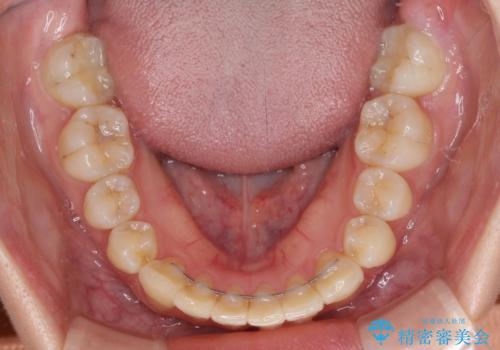

治療途中に出産を迎えるため、下顎前歯のデコボコを部分矯正で改善し、上下前歯を綺麗に仕上げることとしました。

普段は海外在住であり、出産のための一時帰国を利用して短期集中治療を行いました。

自身の出産で大変な時期にもかかわらず、スケジュール通りに通院いただき、望まれたとおりの口元に仕上げることができました。